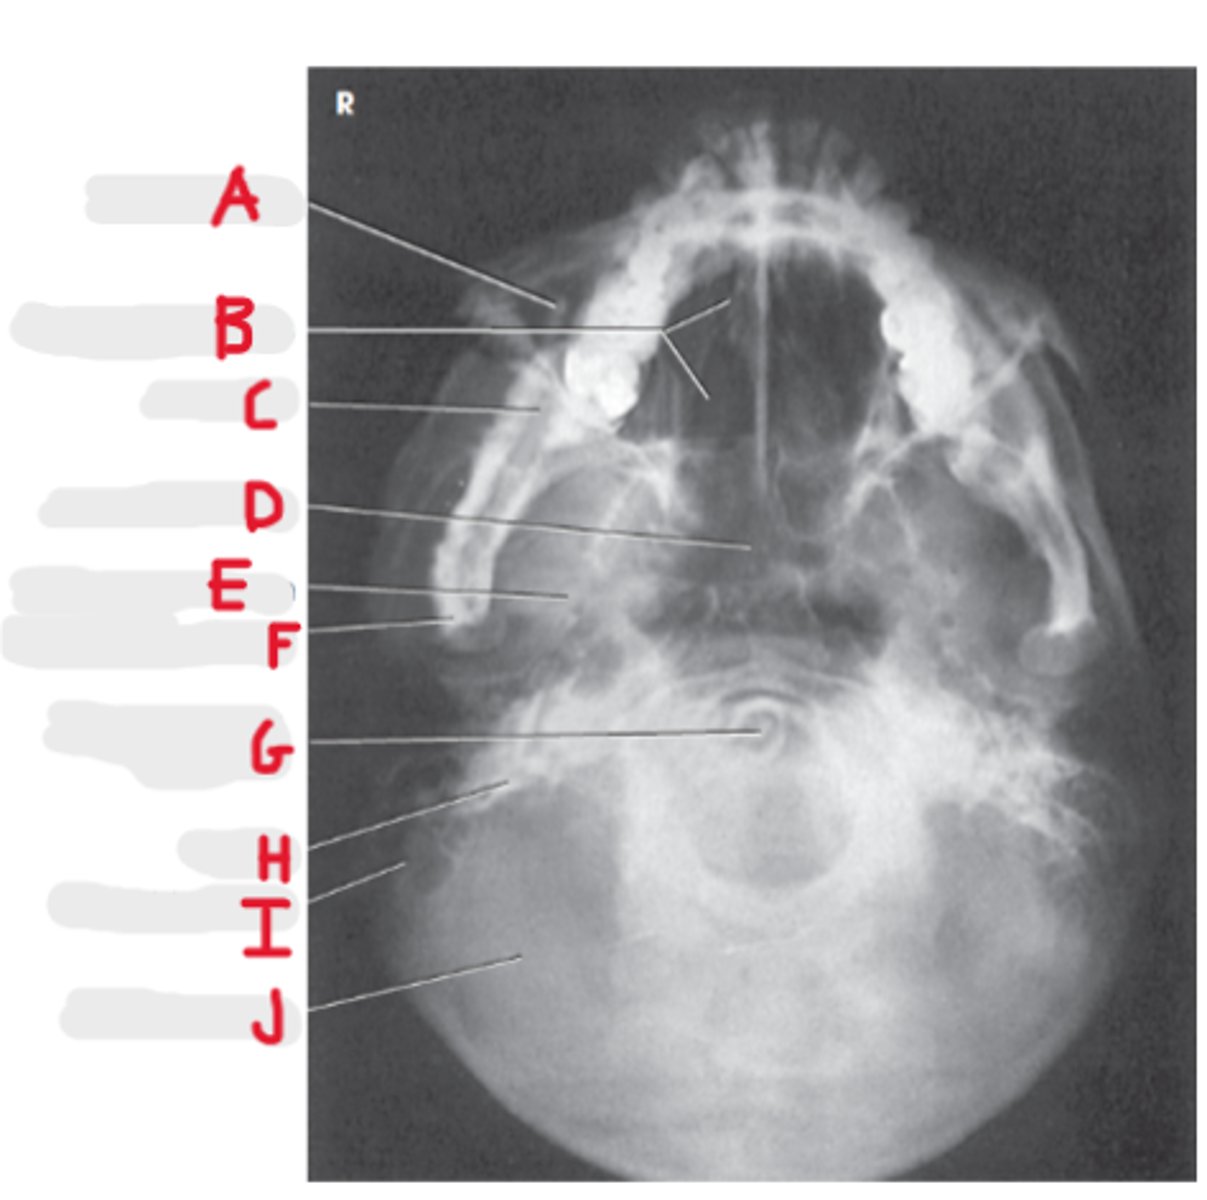

Maxillary sinus

A

Ethmoid air cells

B

Mandible

C

Sphenoid Sinus

D

Foramen spinosum

E

Mandibular condyle

F

Dens or odontoid process

G

Petrosa

H

Mastoid process

I

Occipital bone

J

Parietoacanthial (Waters Method)

What projection is this?

CR to exit at acanthion

What is the CR for the Parietoacanthial (Waters Method)?

MML perpendicular to IR

What line should be perpendicular to the IR on a Parietoacanthial (Waters Method)?

Maxillary Sinuses

What sinuses are best demonstrated on the Parietoacanthial (Waters Method)?

37 degree angle from IR plane

What angle should the OML be at for a Parietoacanthial (Waters Method)?

Equidistant lateral border of skull and lateral borders of the orbits

How do we look for rotation/tilt for the PA Caldwell or Waters?

Pretrous ridges lie inferior to maxillary floor

Where do the petrous ridges (pyramids) lie on a Waters radiograph?